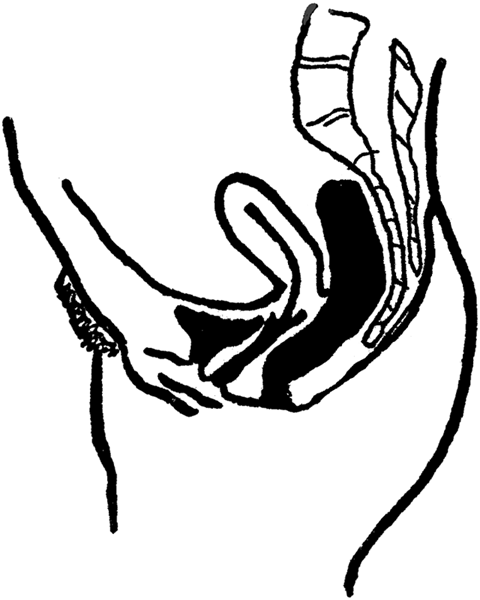

The uterus is situated in the center of the pelvis, between the bladder and the rectum. It is supported by certain ligaments, the chief of which are the broad ligaments; but, on account of general weakness, too hard physical labor, or lifting heavy weights, the ligaments may stretch, and the uterus may sink down low in the vagina, and we then have the condition known as prolapse of the womb. Or, the womb may turn forward, when we have a condition of anteversion. If the womb is bent (or flexed) forward on itself the condition is called anteflexion. If the womb is turned backwards, the condition is called retroversion; if it is bent or flexed backward upon itself the condition is called retroflexion. An extreme degree of anteversion or anteflexion, or retroversion or retroflexion, may interfere with impregnation, as the spermatozoa may find it difficult or impossible to reach the opening of the womb—the external os.

Anteversion of the Uterus.

Anteflexion of the Uterus.